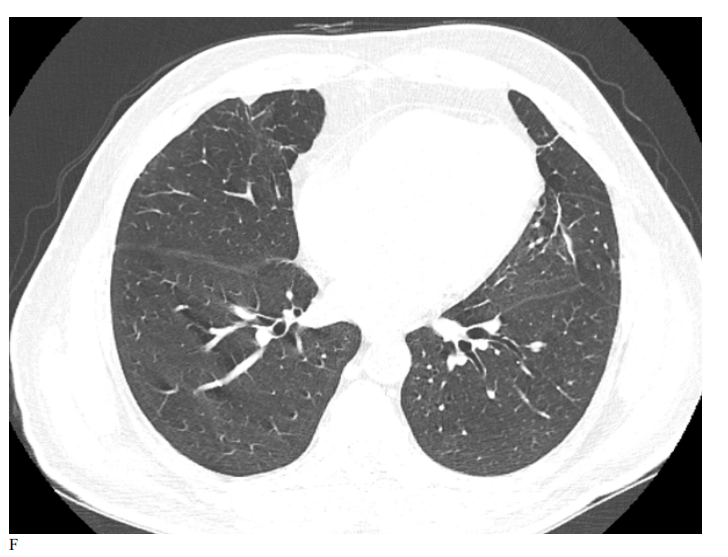

Figure 3: Male patient in NRIZ group shows diffuse bilateral ground glass opacities with alveolar infiltration mainly lower lobes, Covid severity score 12; while figure E After 03 months treatment shows marked resolutions of pervious bilateral pulmonary ground glass opacities and alveolar infiltrates, Covid severity score 6.